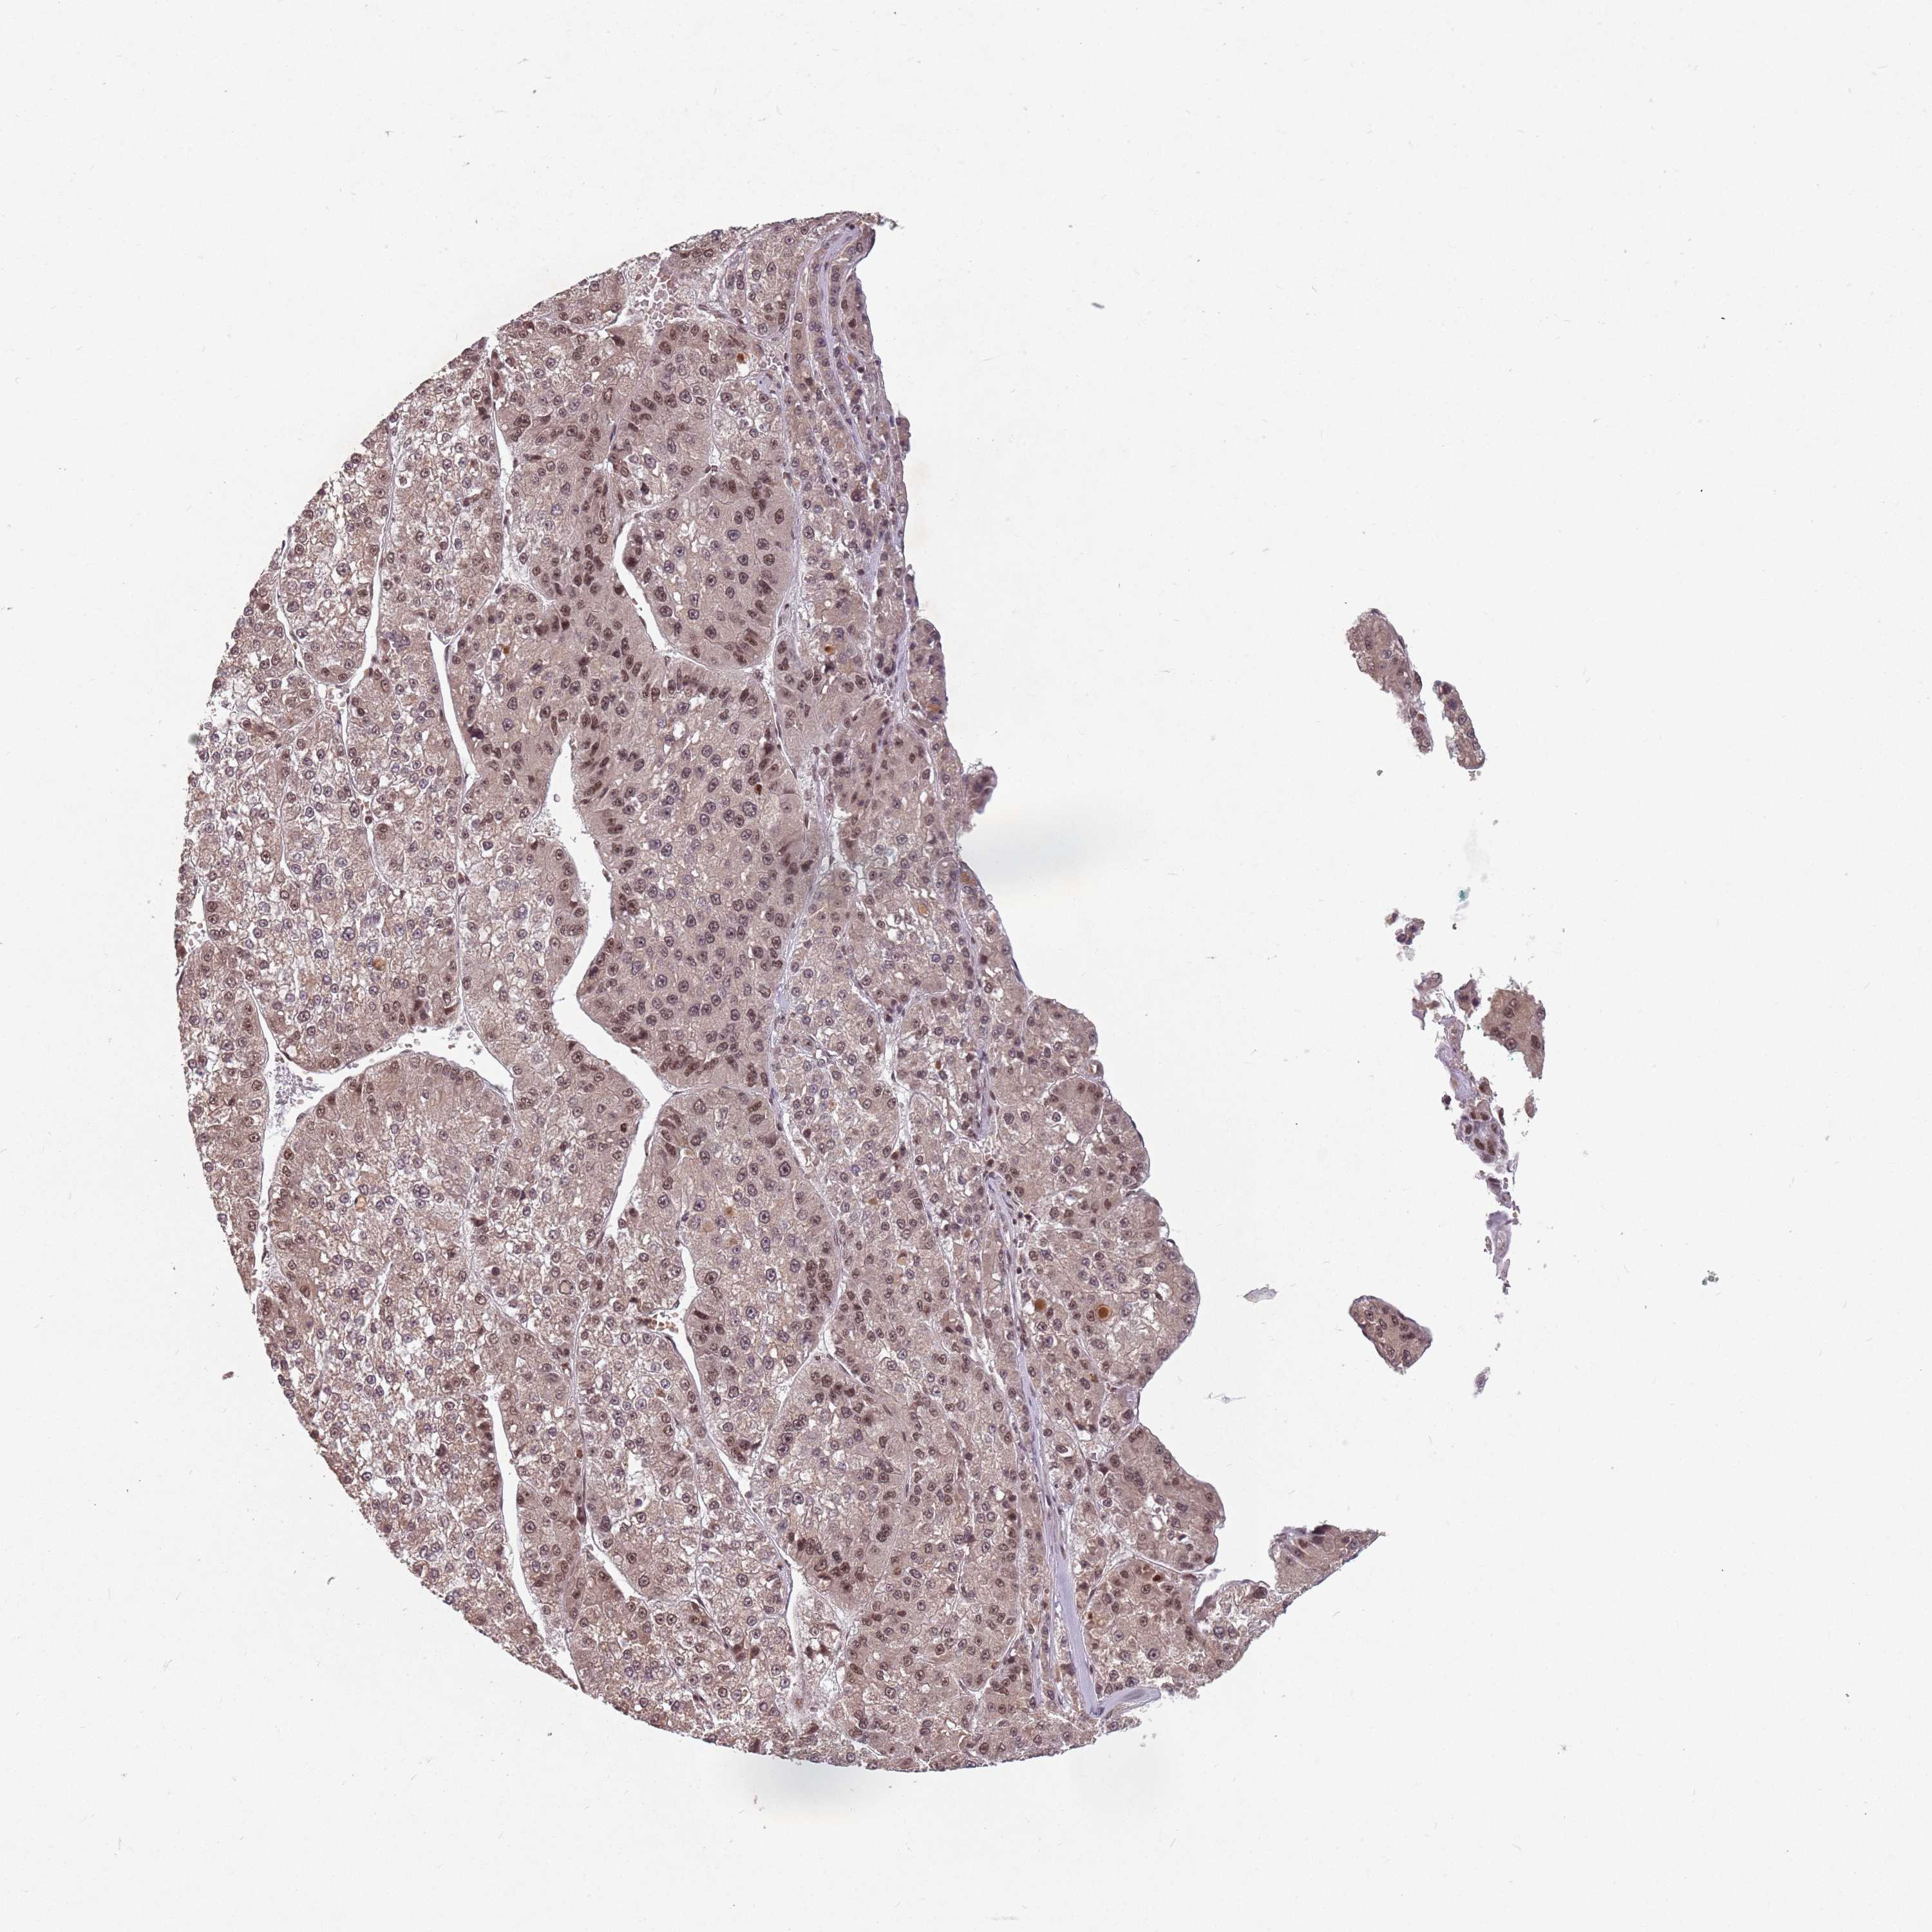

LIVER CANCER - Protein expressioni

A mouse-over function shows sample information and annotation data. Click on an image to view it in a full screen mode. Samples can be filtered based on level of antibody staining by selecting one or several of the following categories: high, medium, low and not detected. The assay and annotation is described here.

Antibody stainingi

Antibody staining in the annotated cell types in the current human tissue is reported as not detected, low, medium, or high, based on conventional immunohistochemistry profiling in selected tissues. This score is based on the combination of the staining intensity and fraction of stained cells.

Each image is clickable and will lead to virtual microscopy that enables deeper exploration of all samples and also displays staining intensity scores, fraction scores and subcellular localization as well as patient and tissue information for each sample.

Antibody HPA049031

Staining

High

Medium

Low

Not detected

Intensity

Strong

Moderate

Weak

Negative

Quantity

>75%

75%-25%

<25%

None

Location

Nuclear

Cytoplasmic/membranous

Cytoplasmic/membranous,nuclear

Cholangiocarcinoma

Carcinoma, Hepatocellular, NOS